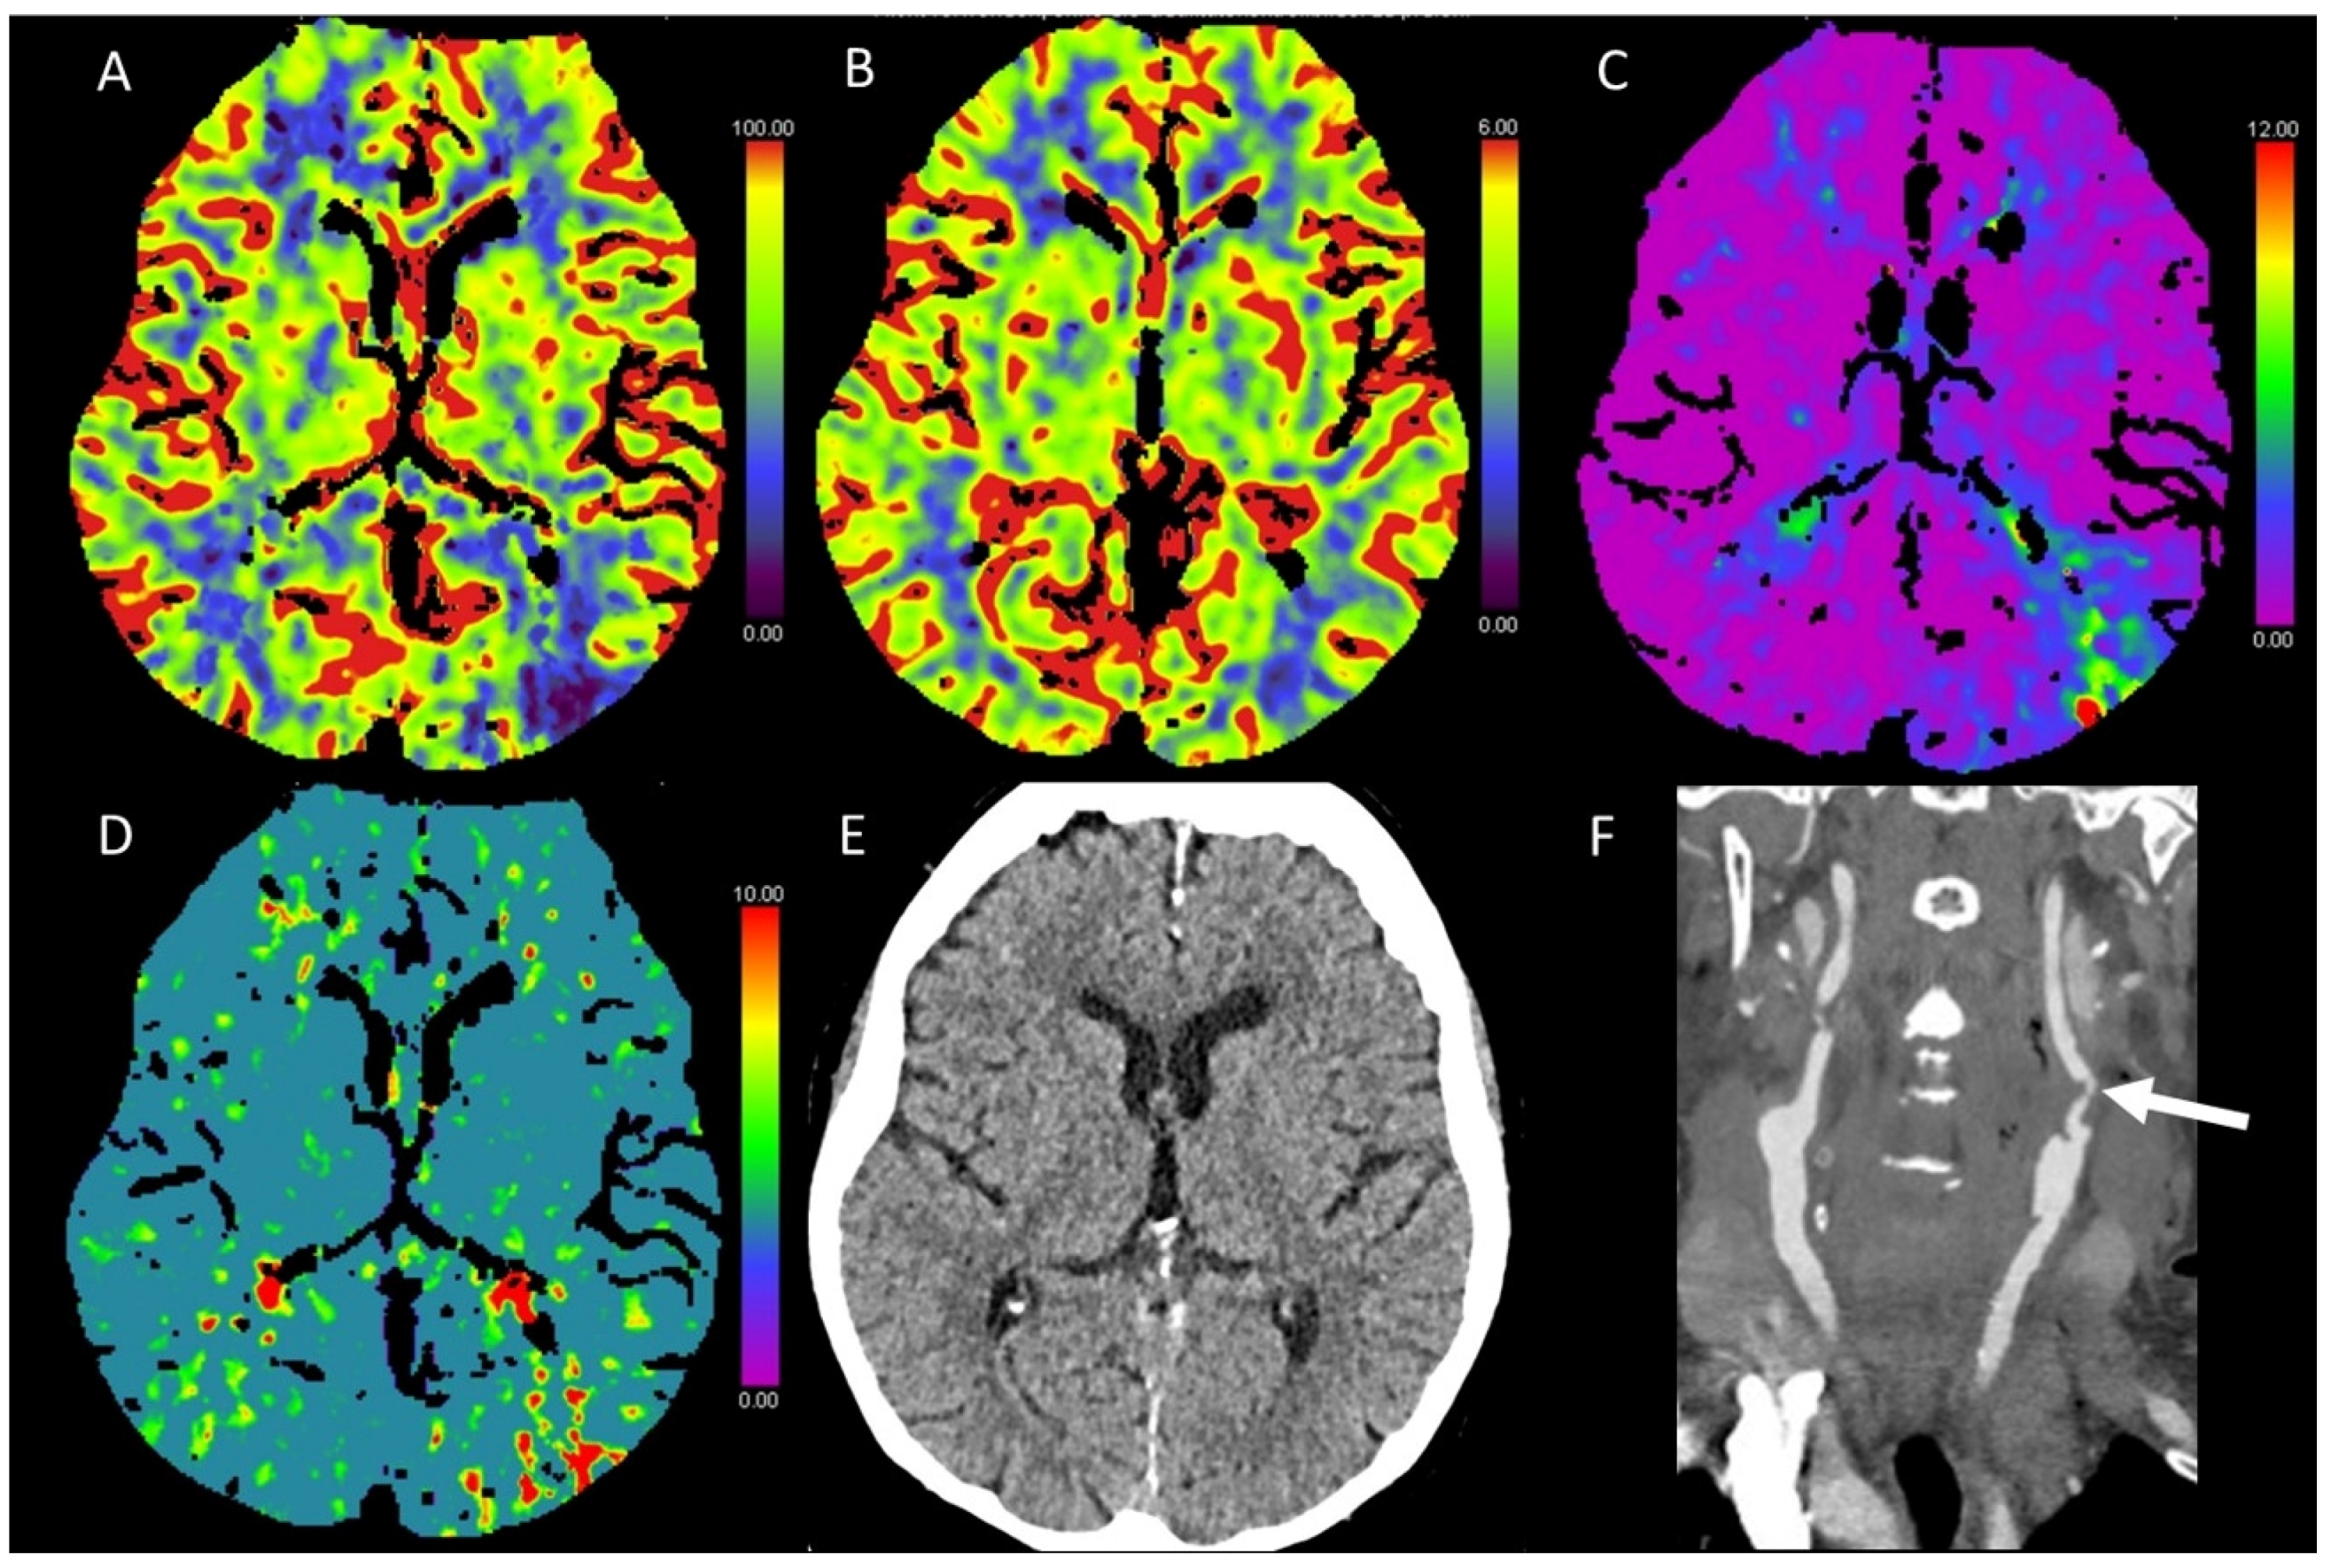

3.6. Vasospasm

| Vasospasm | -/↓ | -/↓ | ↑ | ↑ |